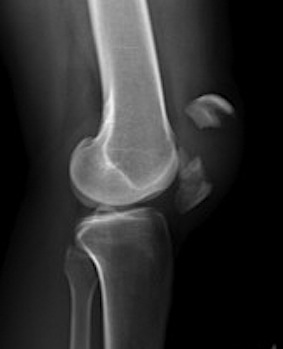

Types

1. Vertical

2. Transverse

3. Burst / Stellate

Displaced transverse fractures

1. TBW

2. Cerclage wire +/- ORIF

- stellate fractures